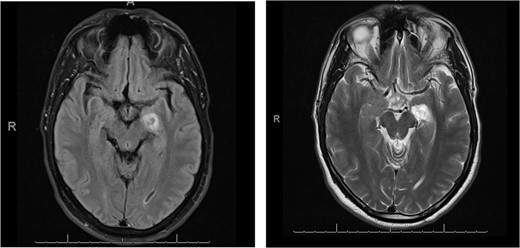

In regard to the new neurological manifestation we performed a brain magnetic resonance imaging (MRI). This demonstrated in the diffusion-weighted imaging (DW-MRI) an ischemic area in the posterior limb of capsula interna and a ring-shaped lesion in the thalamus, showing in Fig. 2. Moreover it appeared a contrast agent enhancement of 5-mm temporal, which was evaluated as a sing of residual tumor. During the inpatient stay we initiated physiotherapy and ergotherapy, which both resulted to a gradually improvement in clinical performance. In the meantime the histological finding revealed a pilocytic astrocytoma, WHO grad I.

Axial diffusion-weighted MRI shows restricted diffusion in the posterior limb of internal capsule.